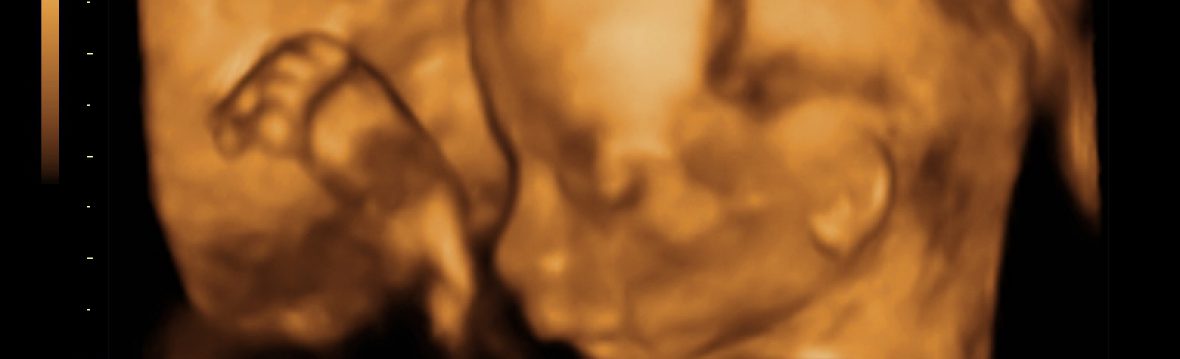

L’ecografia in ostetricia

L'ecografia in gravidanza L’ecografia è entrata prepotentemente nel mondo dell’ostetrica e della gravidanza, tanto da rivoluzionarne tutto l’approccio e creare una nuova branca, ovvero quella della medicina fetale. La medicina fetale attraverso l’uso degli ultrasuoni ha permesso lo studio del comparto uterino e fetale dando anche la possibilità di effettuare procedure diagnostiche e terapeutiche invasive. In particolare,… Continua a leggere L’ecografia in ostetricia